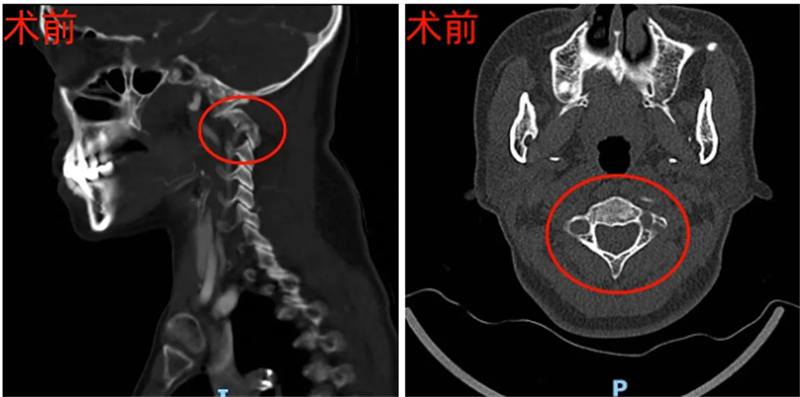

53歲的韋女士長(zhǎng)期飽受反復(fù)后頸部劇痛和肢體麻木折磨,生活質(zhì)量大打折扣。經(jīng)檢查評(píng)估,韋女士被確診患有極其兇險(xiǎn)的寰樞關(guān)節(jié)脫位、顱底凹陷癥并脊髓受壓,意味著連接頭顱與頸椎的關(guān)鍵“生命中樞”正遭受嚴(yán)重壓迫,如不及時(shí)有效干預(yù),可能導(dǎo)致癱瘓甚至危及生命。

本次手術(shù)面臨三大核心難點(diǎn):需將脫位的寰樞椎準(zhǔn)確復(fù)位,毫米級(jí)偏差或力度不當(dāng)就可能損傷脊髓、延髓,風(fēng)險(xiǎn)極高;患者屬“難復(fù)性脫位”,狹小的寰樞椎側(cè)塊關(guān)節(jié)間隙被瘢痕、骨贅填充粘連,需在有限空間內(nèi)精細(xì)松解,堪比“懸崖微雕”;且存在雙側(cè)椎動(dòng)脈高跨,如同手術(shù)通道上的“高壓線”,術(shù)中操作稍失誤就可能損傷椎動(dòng)脈,引發(fā)致命大出血或腦干梗塞。